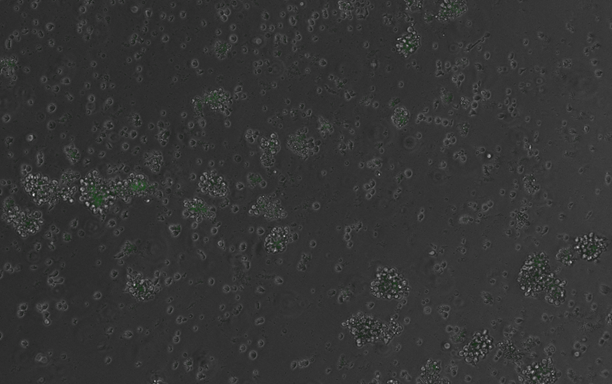

El estudio, llevado a cabo por investigadores del CRG y la UPF, aborda este problema mediante el uso de la inteligencia artificial para diseñar miles de secuencias de ADN sintéticas, cada una con una combinación diferente de motivos de unión. Estos motivos son secuencias muy cortas de nucleótidos que pueden atraer a ciertas proteínas llamadas factores de transcripción. Estas proteínas son clave, ya que se unen a los potenciadores y activan o bloquean los genes. Los investigadores evaluaron estas secuencias en un modelo de diferenciación de células sanguíneas, mediante el uso de tecnologías de análisis paralelo y masivo de reporteros. Esta tecnología permite el estudiar miles de secuencias diferentes al mismo tiempo. Este enfoque ha permitido descifrar algunas de las reglas que rigen el funcionamiento de estos interruptores genéticos en diferentes contextos celulares.